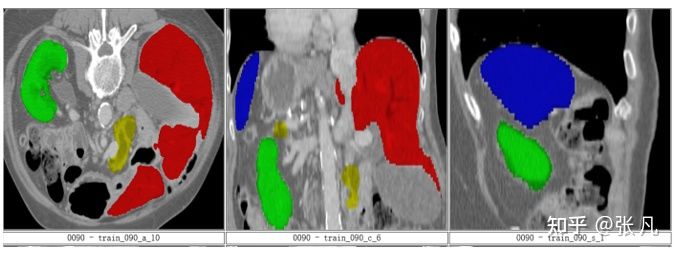

badcase主要包括器官病变和器官缺失,尤其是肾脏、肝脏病变case较多。

肾脏病变:

胰腺病变:

器官缺失: